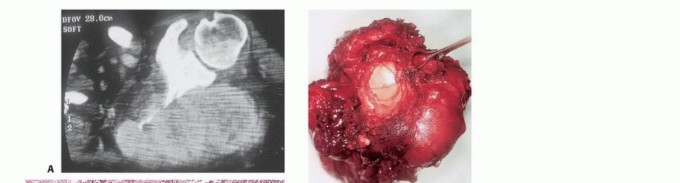

- Computed Tomography (CT): The modality of choice for assessing fine osseous detail, cortical integrity, and matrix mineralization. Thin-slice (≤1 mm) helical CT allows for precise 3D reconstructions. Intravenous contrast is essential to delineate the relationship of the soft tissue mass to major vascular bundles. Chest CT is mandatory for staging to rule out pulmonary metastases.

- Magnetic Resonance Imaging (MRI): The gold standard for evaluating the local extent of the tumor. It accurately defines the intramedullary extent (allowing calculation of bone resection levels), soft tissue extension, joint involvement, and the presence of skip metastases. T1-weighted images best define marrow replacement; T2-weighted and STIR sequences highlight peritumoral edema and the soft tissue mass. Contrast enhancement differentiates cystic from solid components and clarifies neurovascular proximity.

- Angiography and Venography: While largely supplanted by CT/MR Angiography, traditional angiography can map complex vascular displacements, identify feeding vessels for preoperative embolization (critical for hypervascular metastases like renal cell carcinoma), and assess the patency of collateral circulation prior to major vessel ligation. Venography can identify tumor thrombus or extrinsic venous compression.